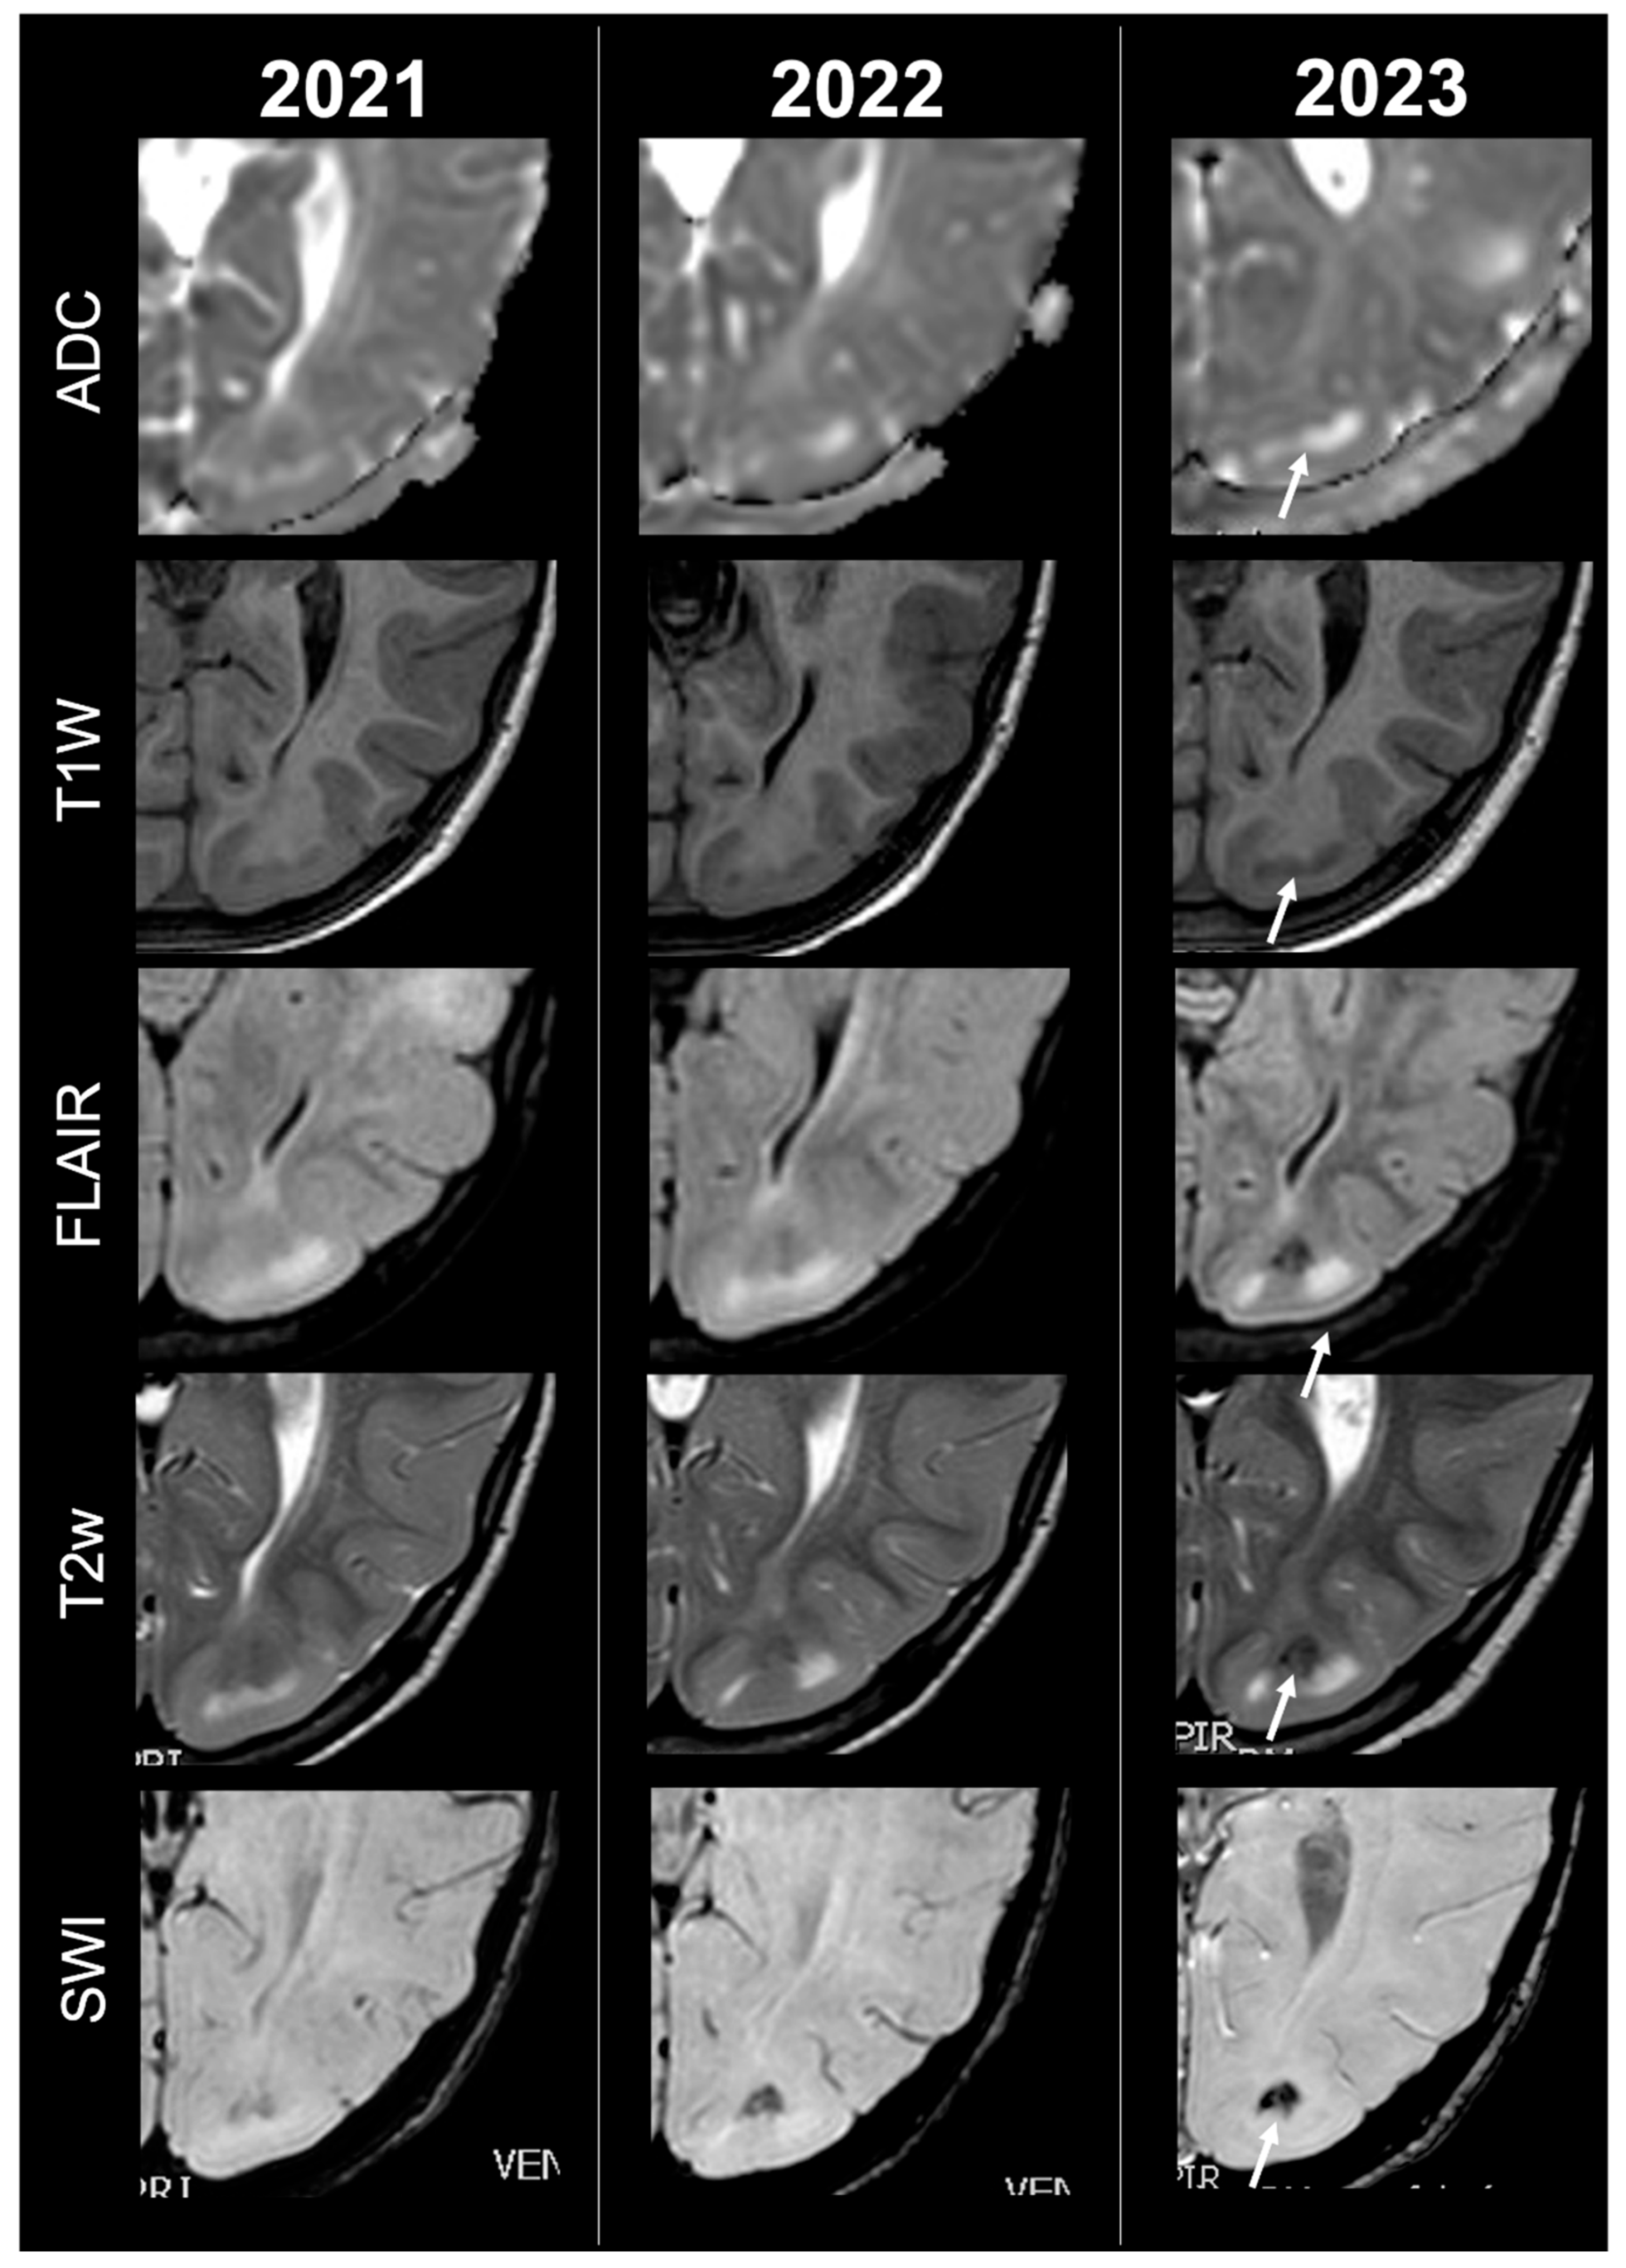

Concerning total lesion count, the interobserver agreement was excellent, with an ICC of 0.91 (95% CI: 0.87–0.95). At baseline, the total number of CTs identified across the cohort was 918 (mean ± SD = 16.1 ± 12.4), whereas at the last available MRI follow-up, the overall count increased to 1070 (mean ± SD = 18.8 ± 13.3), corresponding to a net gain of 152 CTs, equal to a relative variation of +17%. When stratified by tuber type, distinct trajectories were observed over time. Type A CTs, which were relatively abundant at diagnosis (N = 303, mean ± SD = 5.3 ± 7.0), decreased to 255 (mean ± SD = 4.5 ± 5.9) at follow-up, yielding a reduction of 48 lesions (−16%). Conversely, type B CTs showed an opposite trend, increasing from 438 (mean ± SD = 7.7 ± 8.4) at baseline to 556 (mean ± SD = 9.8 ± 8.6) at follow-up, corresponding to a net increase of 118 tubers (+27%). An example of MRI signal evolution from tuber A to tuber B is shown in Figure 1. Similarly, type C1 CTs rose from 160 (mean ± SD = 2.8 ± 4.8) to 220 (mean ± SD = 3.9 ± 5.8), with a net gain of 60 tubers (+38%). Type C2 CTs, initially rare at diagnosis (N = 14, mean ± SD = 0.2 ± 0.8), markedly expanded to 33 (mean ± SD = 0.6 ± 1.5), accounting for an increase of 19 CTs (+136%). Finally, type D CTs were only sporadically encountered, with a modest increase from 3 (mean ± SD = 0.1 ± 0.3) to 6 (mean ± SD = 0.1 ± 0.4), equating to a 100% variation. The observed increment of type C2 tubers was attributable almost exclusively to the progressive transformation of pre-existing type B lesions and, more prominently, type C1 lesions, while the increase in type C1 tubers reflected the gradual conversion of both type A and type B CTs that were already detectable at disease onset. An example of MRI signal evolution from tuber B to C1 is shown in Figure 2, while from tuber C1 to C2 in Figure 3. Only in one patient was a type C1 tuber newly identified at follow-up without clear evidence at baseline. In contrast, newly apparent tubers emerging over time but not clearly visible on baseline scans were most frequently represented by type A and type B lesions. Type D tubers were rare overall and were identified in only six lesions from four patients with a particularly high lesion burden; in all but one case they represented the evolution of type A or type B CTs (an example of MRI signal evolution from tuber A to tuber D is shown in Figure 4), while in a single case they were associated with adjacent subtle calcific foci. Overall descriptive data are summarized in Table 1.

Figure 2.

Right temporal tuber transition from type B to C1 at three different timepoints in a male patient diagnosed with TSC2.